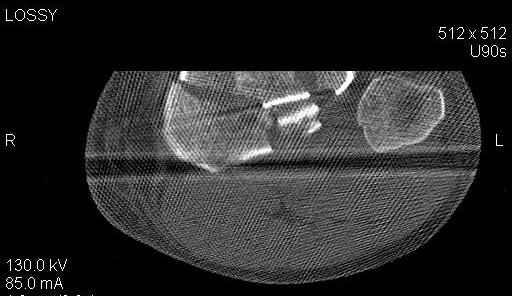

Пациенту сделали КТ - ухитрились сделать на шине Белера (не давал положить прямую ногу) - срезали передний отдел. Планируется на пятницу (24.12) на операцию - синтез длинной мыщелковой LCP-пластиной Synthes :). Отек ближе к слову умеренный (окружность голени +4 см по сравнению со здоровой). КТ и снимок на вытяжении прилагаются.

Здесь как раз тот случай, когда результат зависит не только от мастерства хирурга, но и от наличия современных методов исследования. Например, КТ которая поможет рассчитать направления шурупов и установку импланта. Кроме этого, поможет определиться с доступом.

На представленных предоперационных срезах КТ огромный задне-медиальный фрагмент расположен больше кзади, чем медиально. Для планирования, кроме поперечных срезов, надо ориентироваться на корональные срезы, которые укажут топографию верхушки медиального фрагмента.